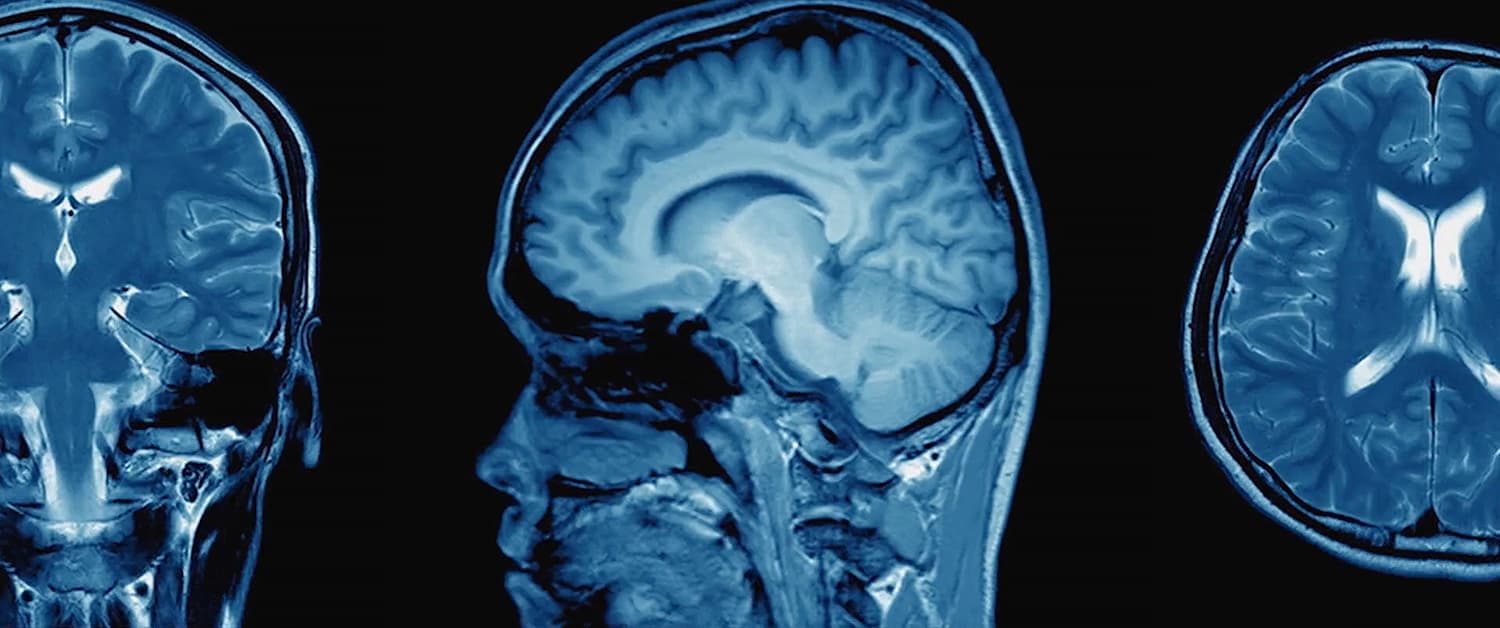

Produced by China Media Group (CMG) and broadcast on China Central Television (CCTV)’s documentary channel, Delving into the Brain, the first documentary series in China to systematically focus on brain science research, has gone viral online and attracted attention from Chinese scientists. The documentary features the achievements of the Tianqiao and Chrissy Chen Institute (TCCI) and acknowledges the support of the TCCI-produced brain science documentary Minds Wide Open at the end of the first episode.

The documentary series consists of six episodes focused on six topics, namely: Planet Brain, Remodeling the Brain, The World inside the Brain, The Strongest Brain, The Opposite Brain and The Brain Map. It took two years of filming and interviews with 40 Chinese key scientific institutes and more than 50 top brain science experts from hospitals including six academicians to complete the production of the documentary. The filming team selected various filming locations such as labs and surgical rooms to create rich content and an easy-to-understand storyline.